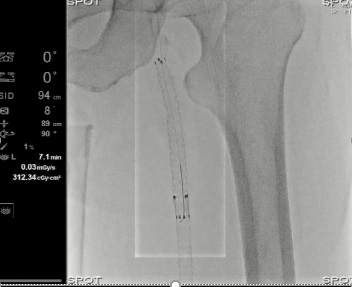

Програмне забезпечення Needle Guidance

Використовується для підтримки навігації при введенні голки в реальному масштабі часу під час перкутанних втручань, таких як біопсія або РЧ абляція.

Ця функція вказує оптимальну для введення голки точку та відстань до наміченої цілі, використовуючи 3D об’єм (ангіо, КТ, МРТ); при цьому зазначається також оптимальне положення С-арки (можливе використання функції 3D авто-кут).